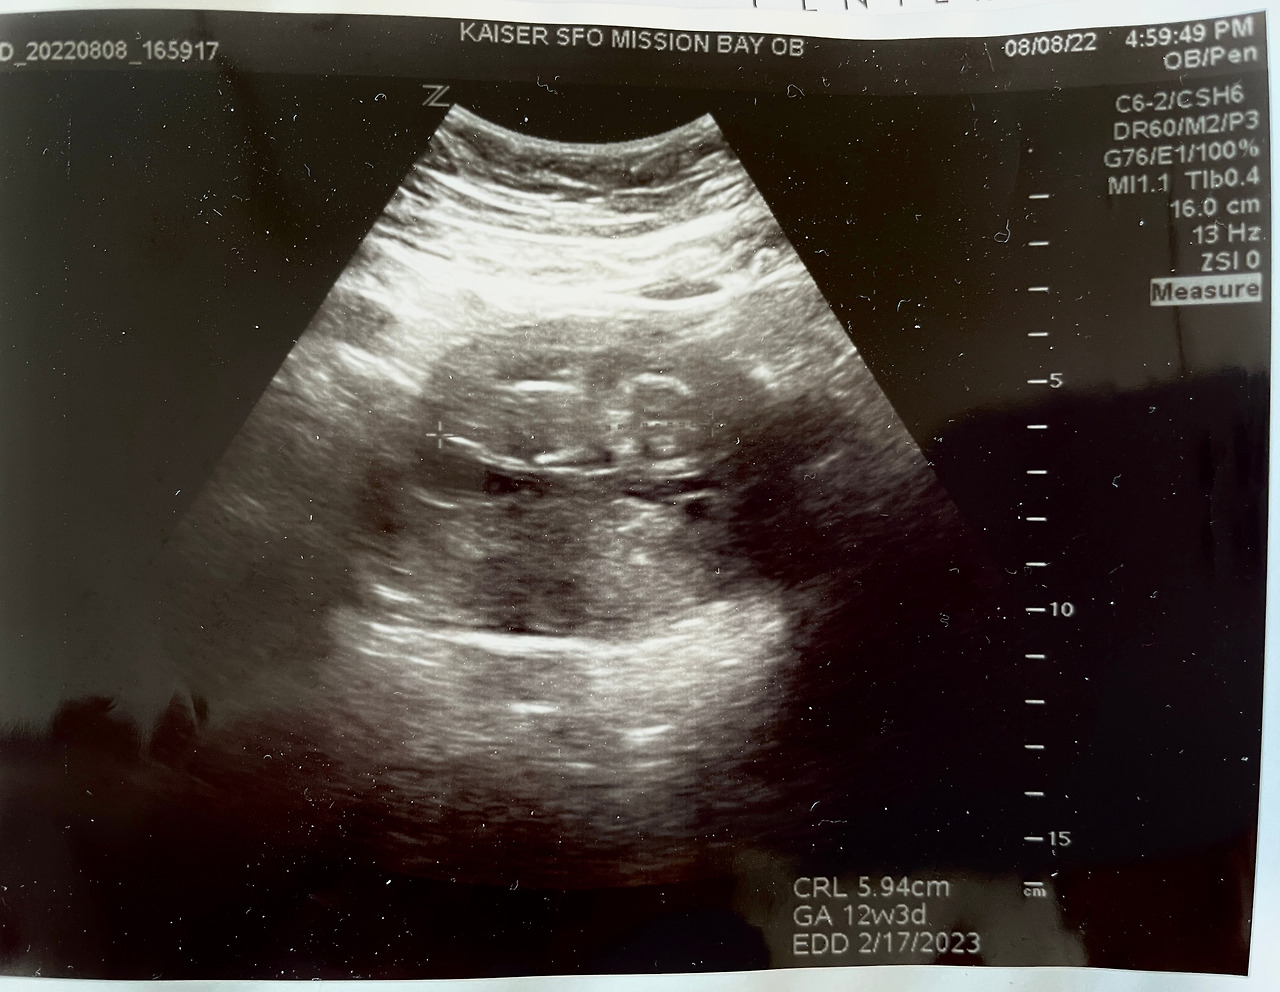

임신 초기 초음파

임신 초기 이야기는 우리 세상이의 8주차, 12주차 초음파 사진과 영상으로 마무리 :)

8주차와 12주차 - 하리보 같이 꼬물거리던 세상이

12주차 - 세상이의 활동적인 꼬물거림을 본 날 (이전까진 계속 딸일거라 추측했는데 이 날 왠지 아들일 것 같았음!)